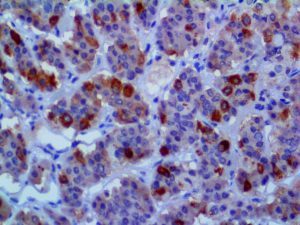

The first cytokines released are interleukin 1β (IL-1β) and tumor necrosis factor-α (TNF-α), which attract a variety of circulating white blood cells (WBCs) to the infection site, including neutrophils, monocytes, macrophages, and natural killer (NK) cells. This response, along with the antipathogenic chemicals released by these cells (i.e., complement), comprise the innate immune response. These cells directly attack the invading pathogen and also release additional cytokines, chief among them interleukin-1 and 6 (IL-6). IL-6 is essential for invoking the adaptive immune response, which calls T-cells, B-cells, and T helper (Th) cells to the infection site. IL-6 also stimulates further recruitment, proliferation and activation of macrophages.

It is the ICU physician who is most likely to witness one of the deadliest manifestations of the abnormal immunological response, the cytokine storm syndrome (CSS). This response is also referred to by some as the cytokine release syndrome (CRS). CSS is characterized by continuous activation and expansion of macrophage and lymphocyte populations, which secrete large amounts of cytokines, causing the cytokine storm. This massive cytokine release is akin to hemophagocytic lymphohistiocytosis (HLH) disease, a syndrome characterized by initial unchecked and persistent activation of cytotoxic T lymphocytes and NK cells.

Clinical and laboratory manifestations of HLH include fever, enlarged liver and/or spleen, neurologic dysfunction, coagulopathy, liver dysfunction, cytopenias (i.e., low levels of erythrocytes, leukocytes, and/or platelets), hypertriglyceridemia, hyperferritinemia, hemophagocytosis, and eventually diminished NK cell activity as the immune system becomes progressively paralyzed. HLH can be familial (primary HLH) or secondary to another disease process (sHLH), such as rheumatic disease, in which it is referred to as macrophage activation syndrome (MAS, characterized by elevated ferritin).